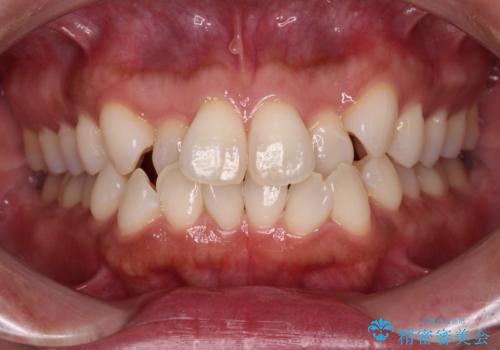

[マウスピース矯正] 海外留学中でも可能な矯正治療

担当医 大元洋佑